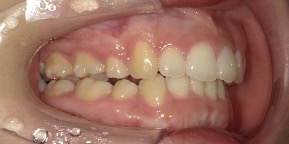

26歳女性のビフォーアフター

| 診断 | 空隙,叢生 |

| 治療方針 | 治療方針:前歯の咬合関係改善と空隙閉鎖を主な目的にて主にIPR(歯と歯の間をわずかに削合してスペースを獲得する方法)を組み込んだ動的矯正治療を行い、空隙、前歯咬合を改善後、保定を行う。臼歯部の咬合関係はプランの都合上維持することとした |

| 治療費 ※ | 69万8千円(診断、型取り、矯正中のメンテナンス、保定装置を含む料金) |

| 治療期間 | 1年8か月 |

| リスク | 1日20時間以上マウスピースを使用できない場合、歯が動かなかったり、想定しない誤差により不完全に終わる可能性がある。装着時や食事時に痛みを伴う。歯肉退縮や虫歯になるおそれがある。また、指導通りに装着できていない場合や適切なブラッシングが出来ていないとそのリスクが高くなる。歯根が短くなることがある。ごくまれに歯の神経が損傷してしまうことがある。過去にぶつけたり深い虫歯治療をしたことがあるとそのリスクはやや高くなる。矯正後には保定装置が必要。適切な使用ができない場合、後戻りの原因となる。将来的に歯並びが動いて再矯正が必要な場合がある。舌癖(舌で歯を押し出す癖)親知らずが正常に生えていない場合、その可能性がやや高くなる。 |

※ 治療費は、治療当時の費用で、現在の費用と異なる可能性があります。現在の費用は治療費のページでご確認くださいませ。